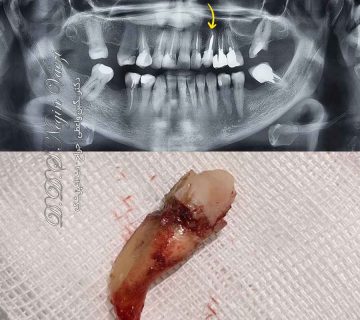

خوشبختانه این بیمار عزیزمون، به موقع برای درمان و کشیدن اقدام کرده بودند که این کار باعث شده بود دندان عقل دچار پوسیدگی یا شکستگی شدید نباشد. در نتیجه کشیدن و خارج سازی دندان عقل ایشان به راحتی و بدون نیاز به جراحی انجام شد. برخی از افراد، کشیدن دندان عقل را بسیار به تاخیر می اندازند. این کار باعث میشود درمان پیچیده تر و البته به دلیل جراحی دندان عقل، پرهزینه تر نیز باشد.

تصویر دندان عقل کشیده شده